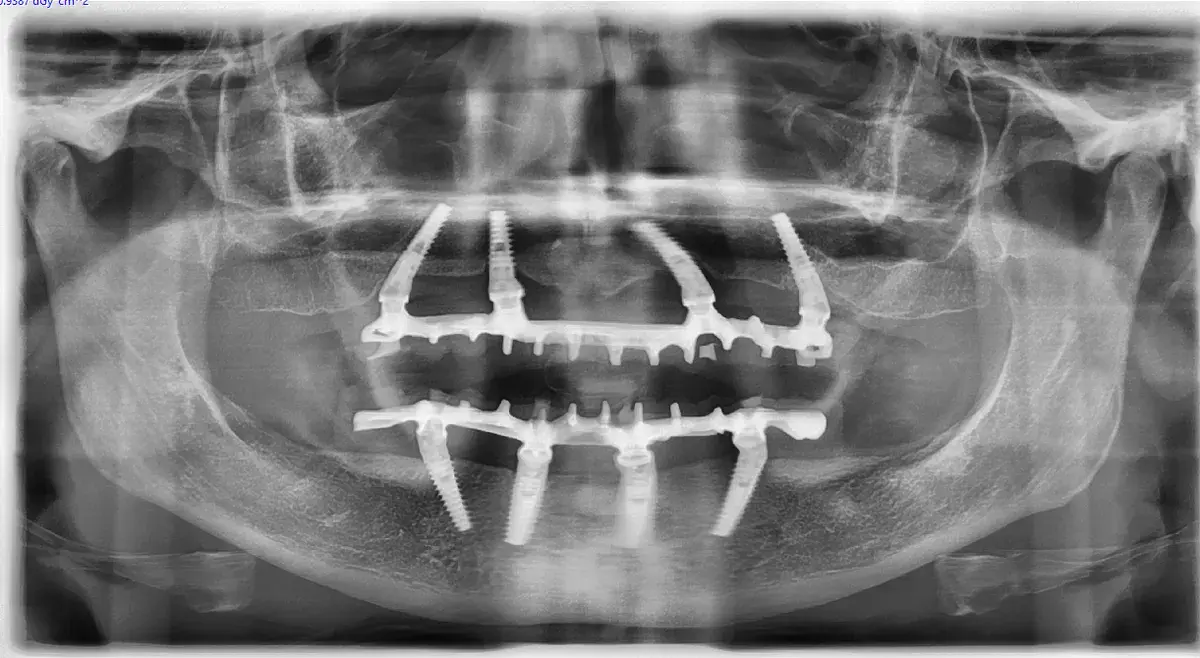

Caso clinico di carico immediato su rialzo crestale del seno mascellare con espansori. Espansione apicale, stabilità >50 Ncm, provvisorio immediato e co...

Esplora il protocollo di espansione apicale, una strategia innovativa per ottenere stabilità ottimale e preservare l’integrità dei tessuti ossei e molli.